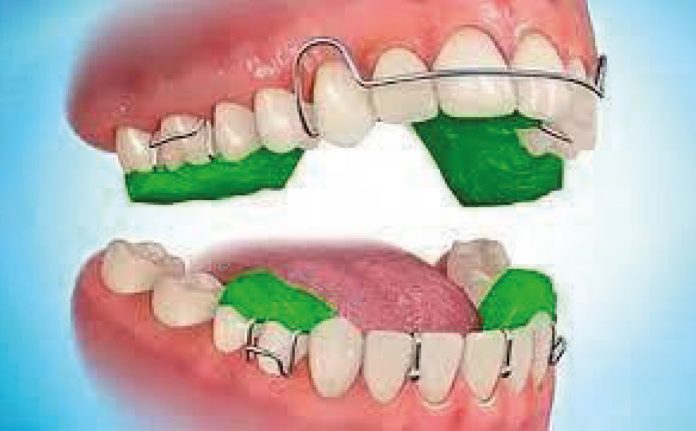

Ultimamente, il Twin Block (fig. 1), sviluppato da William J. Clark, rappresenta l’apparecchio funzionale rimovibile più diffuso e utilizzato per correggere la malocclusione di classe II nei pazienti in fase di crescita. Ciò è attribuibile alla sua crescente popolarità e all’accettabilità dei pazienti nei confronti del dispositivo. Il design separato in due pezzi, uno superiore e uno inferiore, consente una maggiore libertà di parola e masticazione, contribuendo così all’aumento della sua accettazione (4,5).

Il Twin Block può essere impiegato con successo per stimolare e favorire la crescita mandibolare nei pazienti in fase di sviluppo.